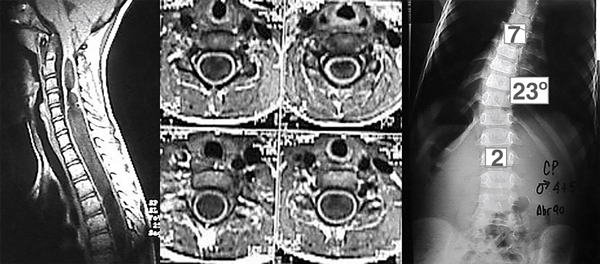

Paciente masculino de 4 años y 6 meses con ausencia de reflejos cutáneos abdominales y una escoliosis torácica de convexidad izquierda, cuyo valor angular de Cobb T-L3 de 230° y convexidad izquierda se trató con corsé toraco-lumbosacro (tipo TLSO). La RM mostró una malformación de Chiari tipo I asociada a una extensa siringomielia, desde C2 a T9 (Figura 1). Los potenciales evocados somatosensoriales (PESS) resultaron normales. Se adoptó conducta expectante.

Figura 1. Cortes sagital y axiales en los que se observa extensa dilatación siringomiélica. Espinograma, frente.